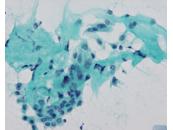

第37回日本臨床細胞学会九州連合会学会(佐賀)スライドカンファレンス症例4

種別:泌尿器

出題:○松山 篤二 福岡和白病院病理診断科

| 年齢 | 68歳 | 性別 | 男性 |

|---|---|---|---|

| 採取部位 | 尿 | 採取方法 | 自然尿 |

| 検体処理法 | 従来法 |

臨床所見

既往歴:大腸癌

現病歴:S状結腸癌ならびに肺転移にて化学療法中。2週間前から排尿困難、残尿感があり、泌尿器科に紹介された。直腸診で前立腺は超胡桃大、全体に固く表面やや不整であった。精査のため、まず尿細胞診が行われた。

(画像2、5~8は同一の倍率です)

| 正解 | 1.大腸癌 |

|---|

▼選択肢及び投票結果

| 1.大腸癌 | 3件 | (3.8%) | |

| 2.前立腺癌 | 44件 | (55.0%) | |

| 3.高異型度尿路上皮癌 | 17件 | (21.2%) | |

| 4.低異型度尿路上皮癌 | 8件 | (10.0%) | |

| 5.反応性尿路上皮 | 8件 | (10.0%) | |

| 投票総数 | 80件 | (100%) |